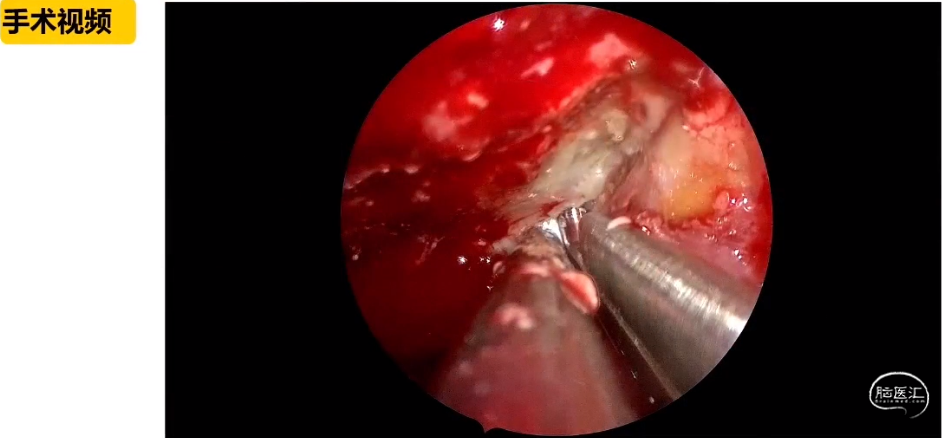

刘庆教授:经鼻内镜技术在复杂颅底肿瘤手术中的应用与思考